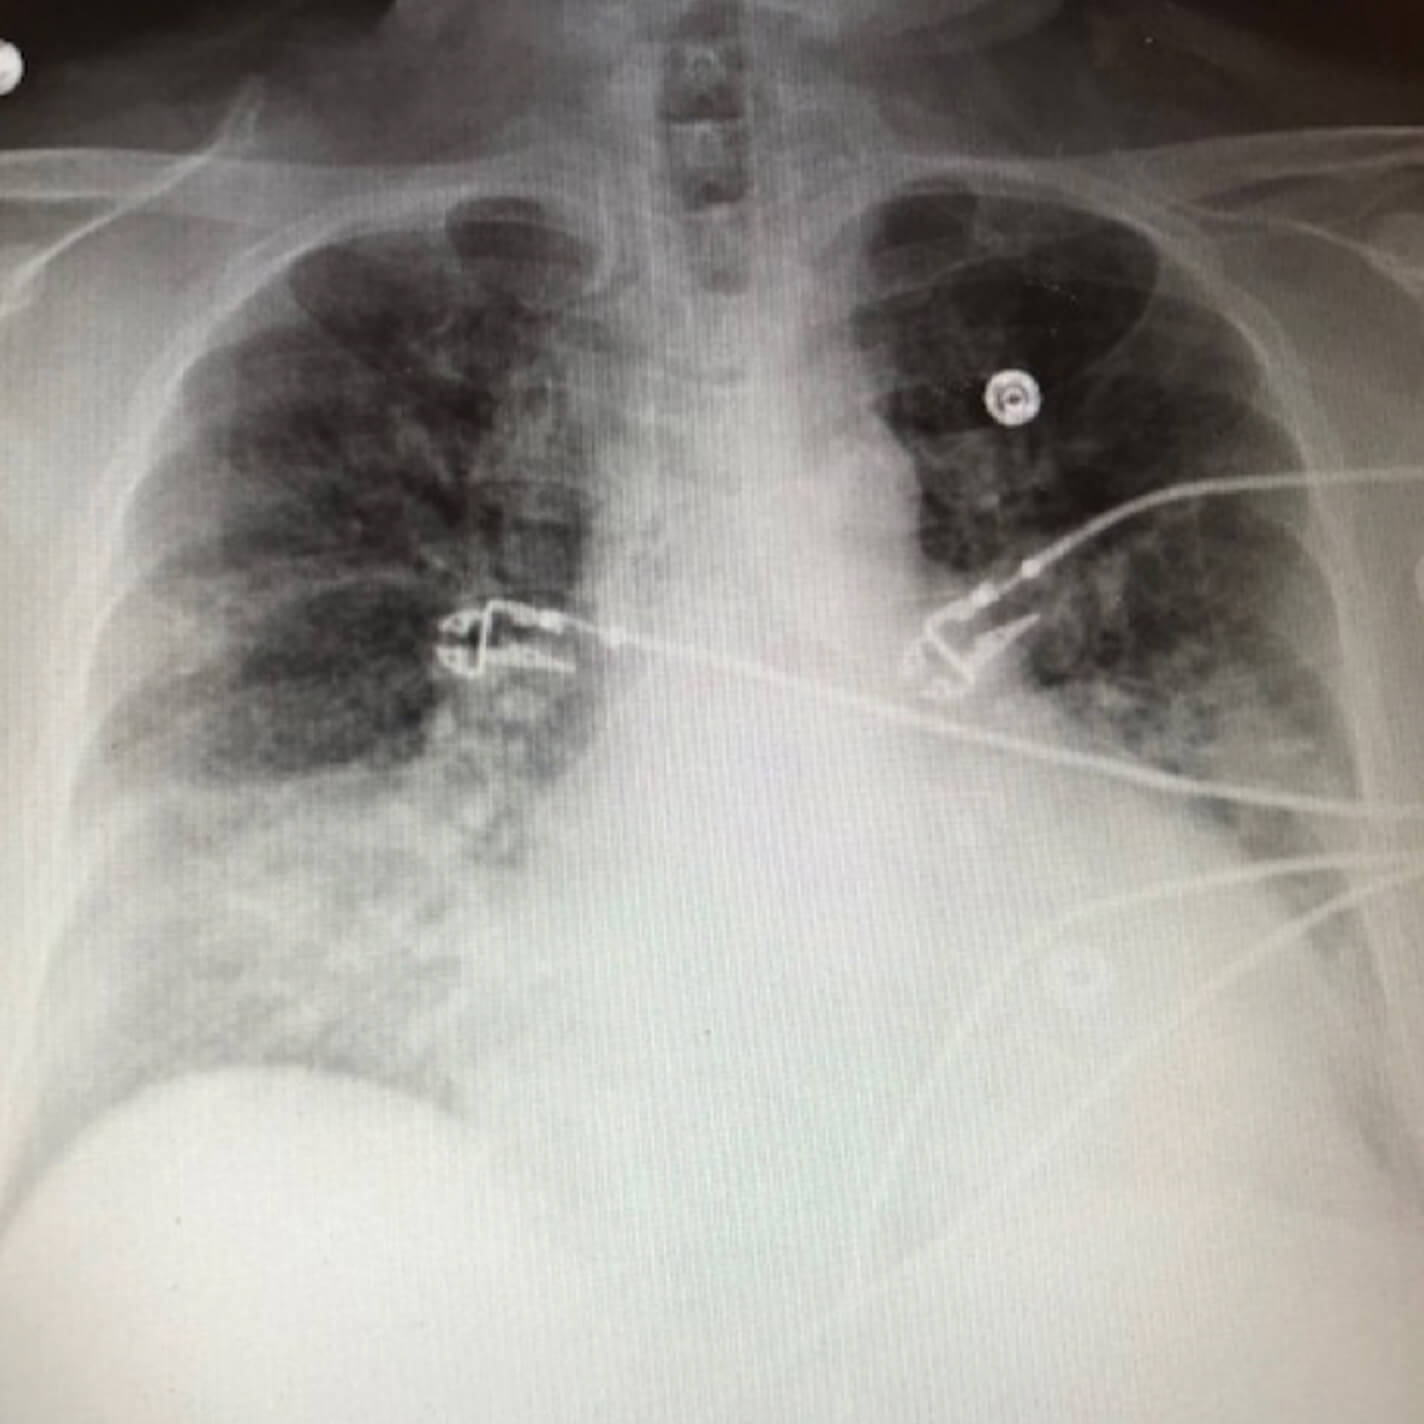

Initial chest x-ray

Before image of an initial chest x-ray.

• Chest x-ray revealed bibasilar opacities with L>R concerning for pneumonia